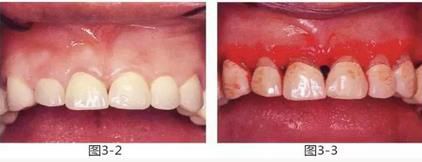

圖3-2 ,3

雖然存在較為淺度的牙周袋和齦下齲壞,但是從齦緣到牙槽嵴頂位置有充足的健全牙體組織和角化齦,因此通過牙齦切除進行了治療。